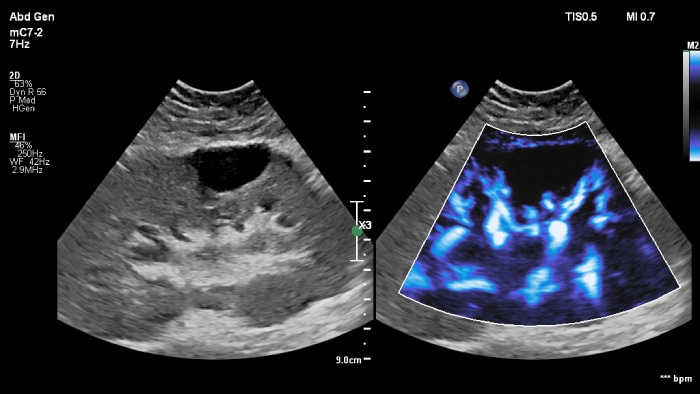

Os ecógrafos da Philips para a radiologia de intervenção suportam uma gama de capacidades sofisticadas para aplicações de intervenção. O fluxo de trabalho otimizado permite aos médicos alcançar uma fusão rápida e eficaz de TAC/RM/PET/CBCT com ecografia em tempo real, enquanto a navegação da agulha ajuda a orientar a biópsia e a ablação das lesões pequenas e de difícil acesso. A fusão e a navegação também podem ser utilizadas em conjunto com a ecografia com realce por contraste (CEUS), dando aos médicos acesso a ferramentas de diagnóstico ainda mais poderosas com visualização avançada.

A fusão e navegação dos ecógrafos da Philips podem ajudá-lo a cumprir os seus objetivos operacionais e de cuidados de saúde do paciente em procedimentos intervencionistas.